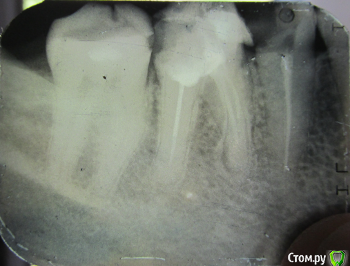

uitod Опубликовано 26 апреля, 2019 Поделиться Опубликовано 26 апреля, 2019 Протезист посмотрел снимок и сказал что не стоит, так как всё рассыпется На фото левая сторона (от меня) нижней челюсти. Ссылка на комментарий

AndyAndy Опубликовано 26 апреля, 2019 Поделиться Опубликовано 26 апреля, 2019 Снять пломбу в 6-ом зубе, оценить состояние твёрдых тканей Перелечивание каналов в 6-ом и 5-ом (он же у вас без пломбы, канал инфицирован)Адекватное восстановление культей зубов (я за культевые вкладки)КоронкиИ ничего не рассыпется Ссылка на комментарий

krokomot Опубликовано 26 апреля, 2019 Поделиться Опубликовано 26 апреля, 2019 помоему фуркации уже нет в 6-ом зубе, прогноз сомнительный, поковырять можно, убрать все некротические ткани и сделать снимок, оценить возможность дальнейшего лечения. Ссылка на комментарий